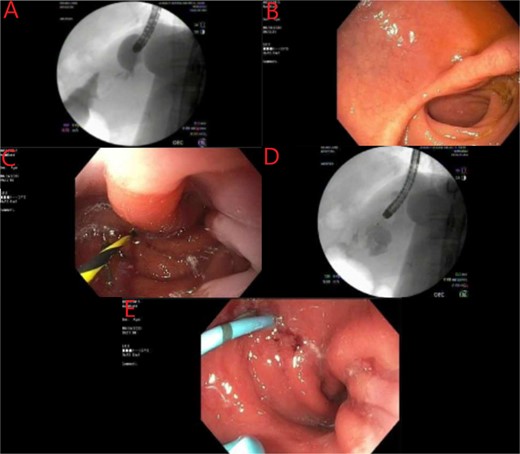

We report a case of a 39-year-old female, with a past medical history significant for morbid obesity status-post SADI-S ⁓3 years prior at an out-of-state medical center who was transferred to our institution with computed tomography (CT) evidence of an intramural abscess near the proximal greater curvature of the stomach as displayed in Fig. 1A. Our patient had a reported weight loss of 99.8 kg since her bariatric surgery and did not encounter any significant issues until this current episode of symptoms began. She was previously treated with a 2-week course of intravenous (IV) antibiotics with minimal symptomatic improvement prior to transfer to our facility. Notably, the patient was treated with oral corticosteroids ⁓1 month before she initially presented to the hospital for a streptococcal infection. She reported being a non-smoker (neither currently nor previously) and also denied recent use of NSAIDs or proton pump inhibitors (PPIs).

(A) CT showing a complex fluid collection at the proximal greater curvature of the stomach consistent with intramural abscess. (B) Interval improvement in complex fluid collection after endoscopic stent removal.

Endoscopic evaluation and stent placement into perforation of the gastric cardia. (A) Delayed imaging of UGI series with no extravasation of contrast. (B) Widely patent duodenal switch lumen. (C) Wire being placed into the fistula tract of the gastric cardia. (D) Contrast filling into the identified abscess cavity. (E) Placement of a double lumen stent through the fistula into the abscess cavity.

The patient’s postprocedure course was complicated with severe epigastric abdominal pain, resulting in repeat EGD and stent removal seven days after placement. A follow up CT was completed which demonstrated improvement in the complex fluid collection as shown in Fig. 1B. Her diet was advanced and the patient was tolerating a full liquid diet by the date of her discharge.